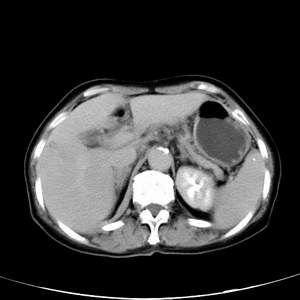

患者,女性,77岁,右上腹胀痛月余。afp正常。ca125升高。即往无肝炎病史。

肝右叶病灶是胆管细胞癌吗?门静脉右支癌栓形成?右侧肾上腺有问题吗?

最后5幅图片是延时7分钟的。门静脉右前支内有充缺吗?如有,肝血管瘤不好解释。

病灶渐进性向心性强化,延时病灶中心见条片状高密度影,局部见肝包膜回缩征,结合病人无肝炎病史,考虑肝右叶胆管细胞癌,门脉右支癌栓形成。